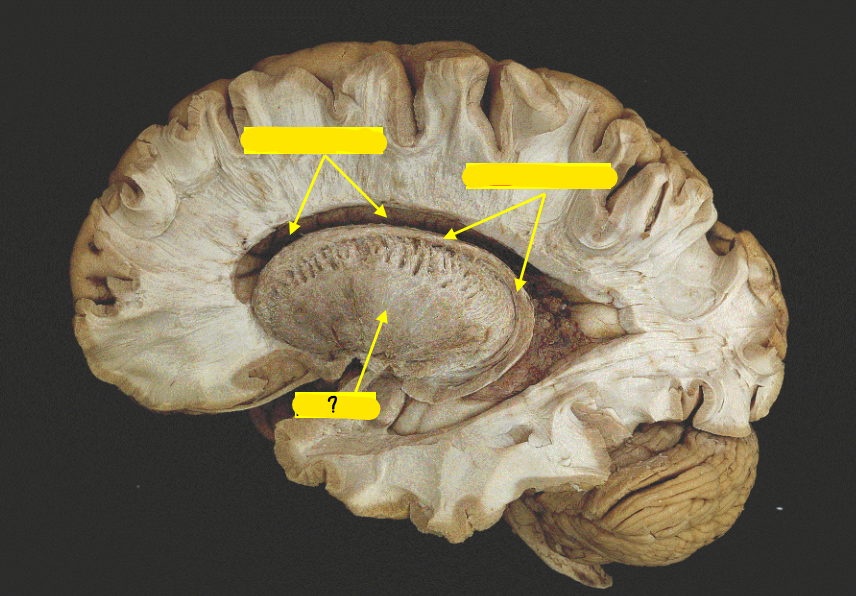

body of caudate nucleus

lateral ventricle

thalamus

internal capsule

putamen

globus pallidus

substantia nigra

inferior horn of lateral ventricle

temporal lobe